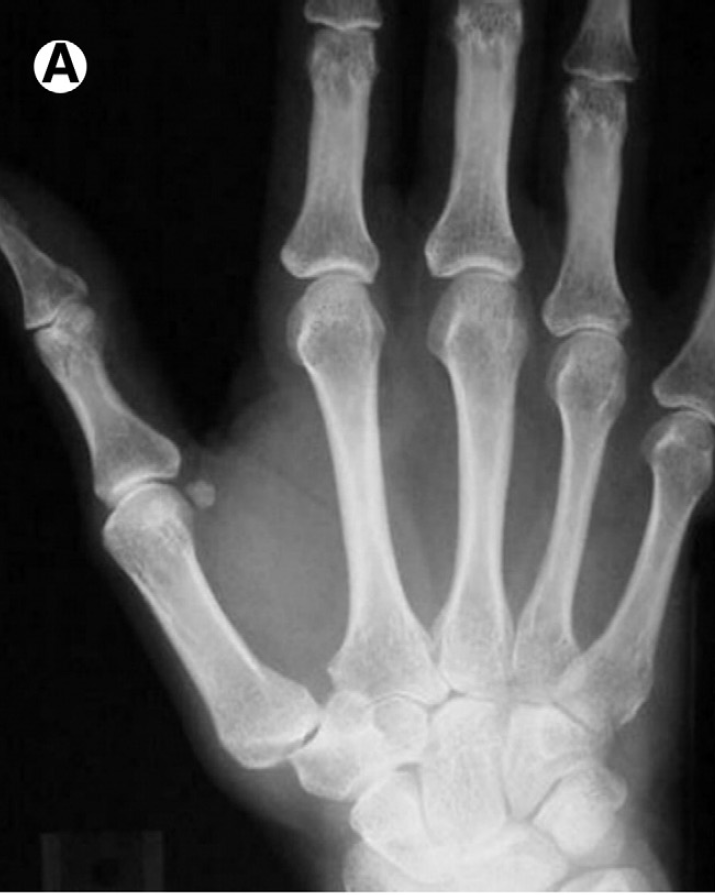

Arthroscopic Options for Treating a Painful, Arthritic Thumb

Health News Digest 2020 Pain relief is more available than ever for treating a painful arthritic thumb, thanks to the development of ever-newer technologies, says Miami-based orthopedic surgeon Alejandro Badia MD. Dr. Badia, a noted specialist in disorders and injuries of the hand, wrist and upper limbs, is using the BioPro® Modular Thumb Implant as… [Read More]